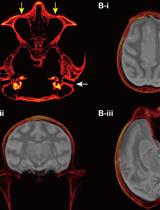

Targeted Delivery of Chemogenetic Adeno-Associated Viral Vectors to Cortical Sulcus Regions in Macaque Monkeys by Handheld Injections

KO Kei Oyama

YN Yuji Nagai

TM Takafumi Minamimoto

1694 Views

Dec 5, 2023

Recent advancements in chemogenetic tools, such as designer receptors exclusively activated by designer drugs (DREADDs), allow the simultaneous manipulation of activity over a specific, broad brain region in nonhuman primates. However, the introduction of DREADDs into large and complexly shaped cortical sulcus regions of macaque monkeys is technically demanding; previously reported methods are time consuming or do not allow the spatial range of expression to be controlled. In the present report, we describe the procedure for an adeno-associated viral vector (AAV2.1) delivery via handheld injections into the dorsolateral prefrontal cortex (Brodmann’s area 9/46) of macaque monkeys, with reference to pre-scanned anatomical magnetic resonance images. This procedure allows the precise delivery of DREADDs to a specific cortical region.Key features• This article describes the procedures for injecting viral vectors encoding functional proteins for chemogenetic manipulation into targeted cortical sulcus regions.• The protocol requires magnetic resonance imaging for the accurate estimation of the injection sites prior to surgery.• Viral vector solutions are injected using a handheld syringe under microscopic guidance.• This protocol allows for the precise introduction of designer receptors exclusively activated by designer drugs (DREADDs) to large and complex cortical regions.